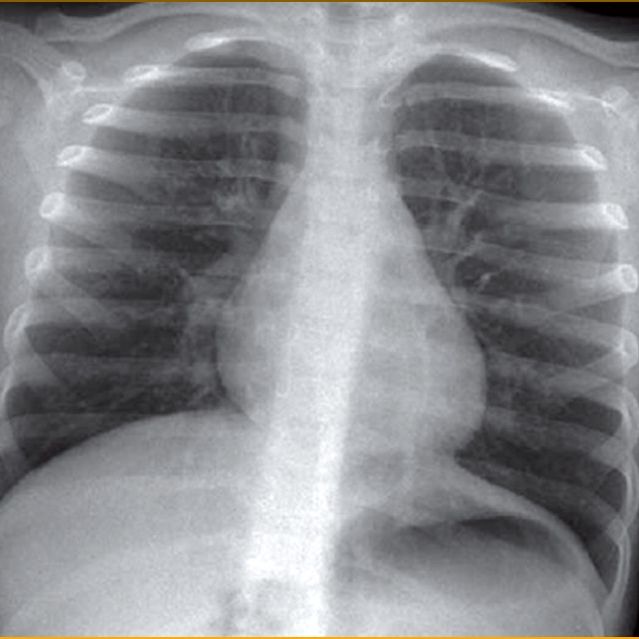

Radiografia del Torace normale

Radiografia del Torace in Espirio

Si vede chiaramente la mancata espulsione dell'aria dal campo polmonare a sinistra per occlusione bronchiale